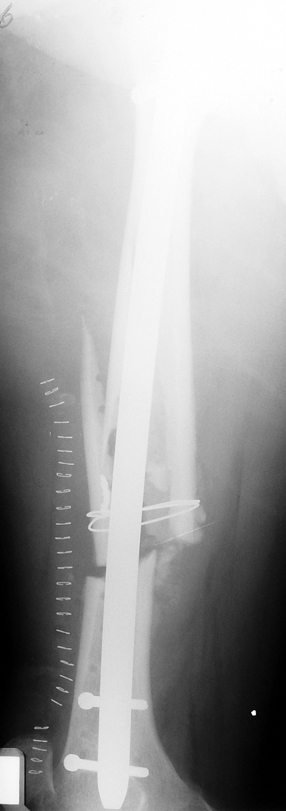

Femur Pseudartrhrosis

Case 1